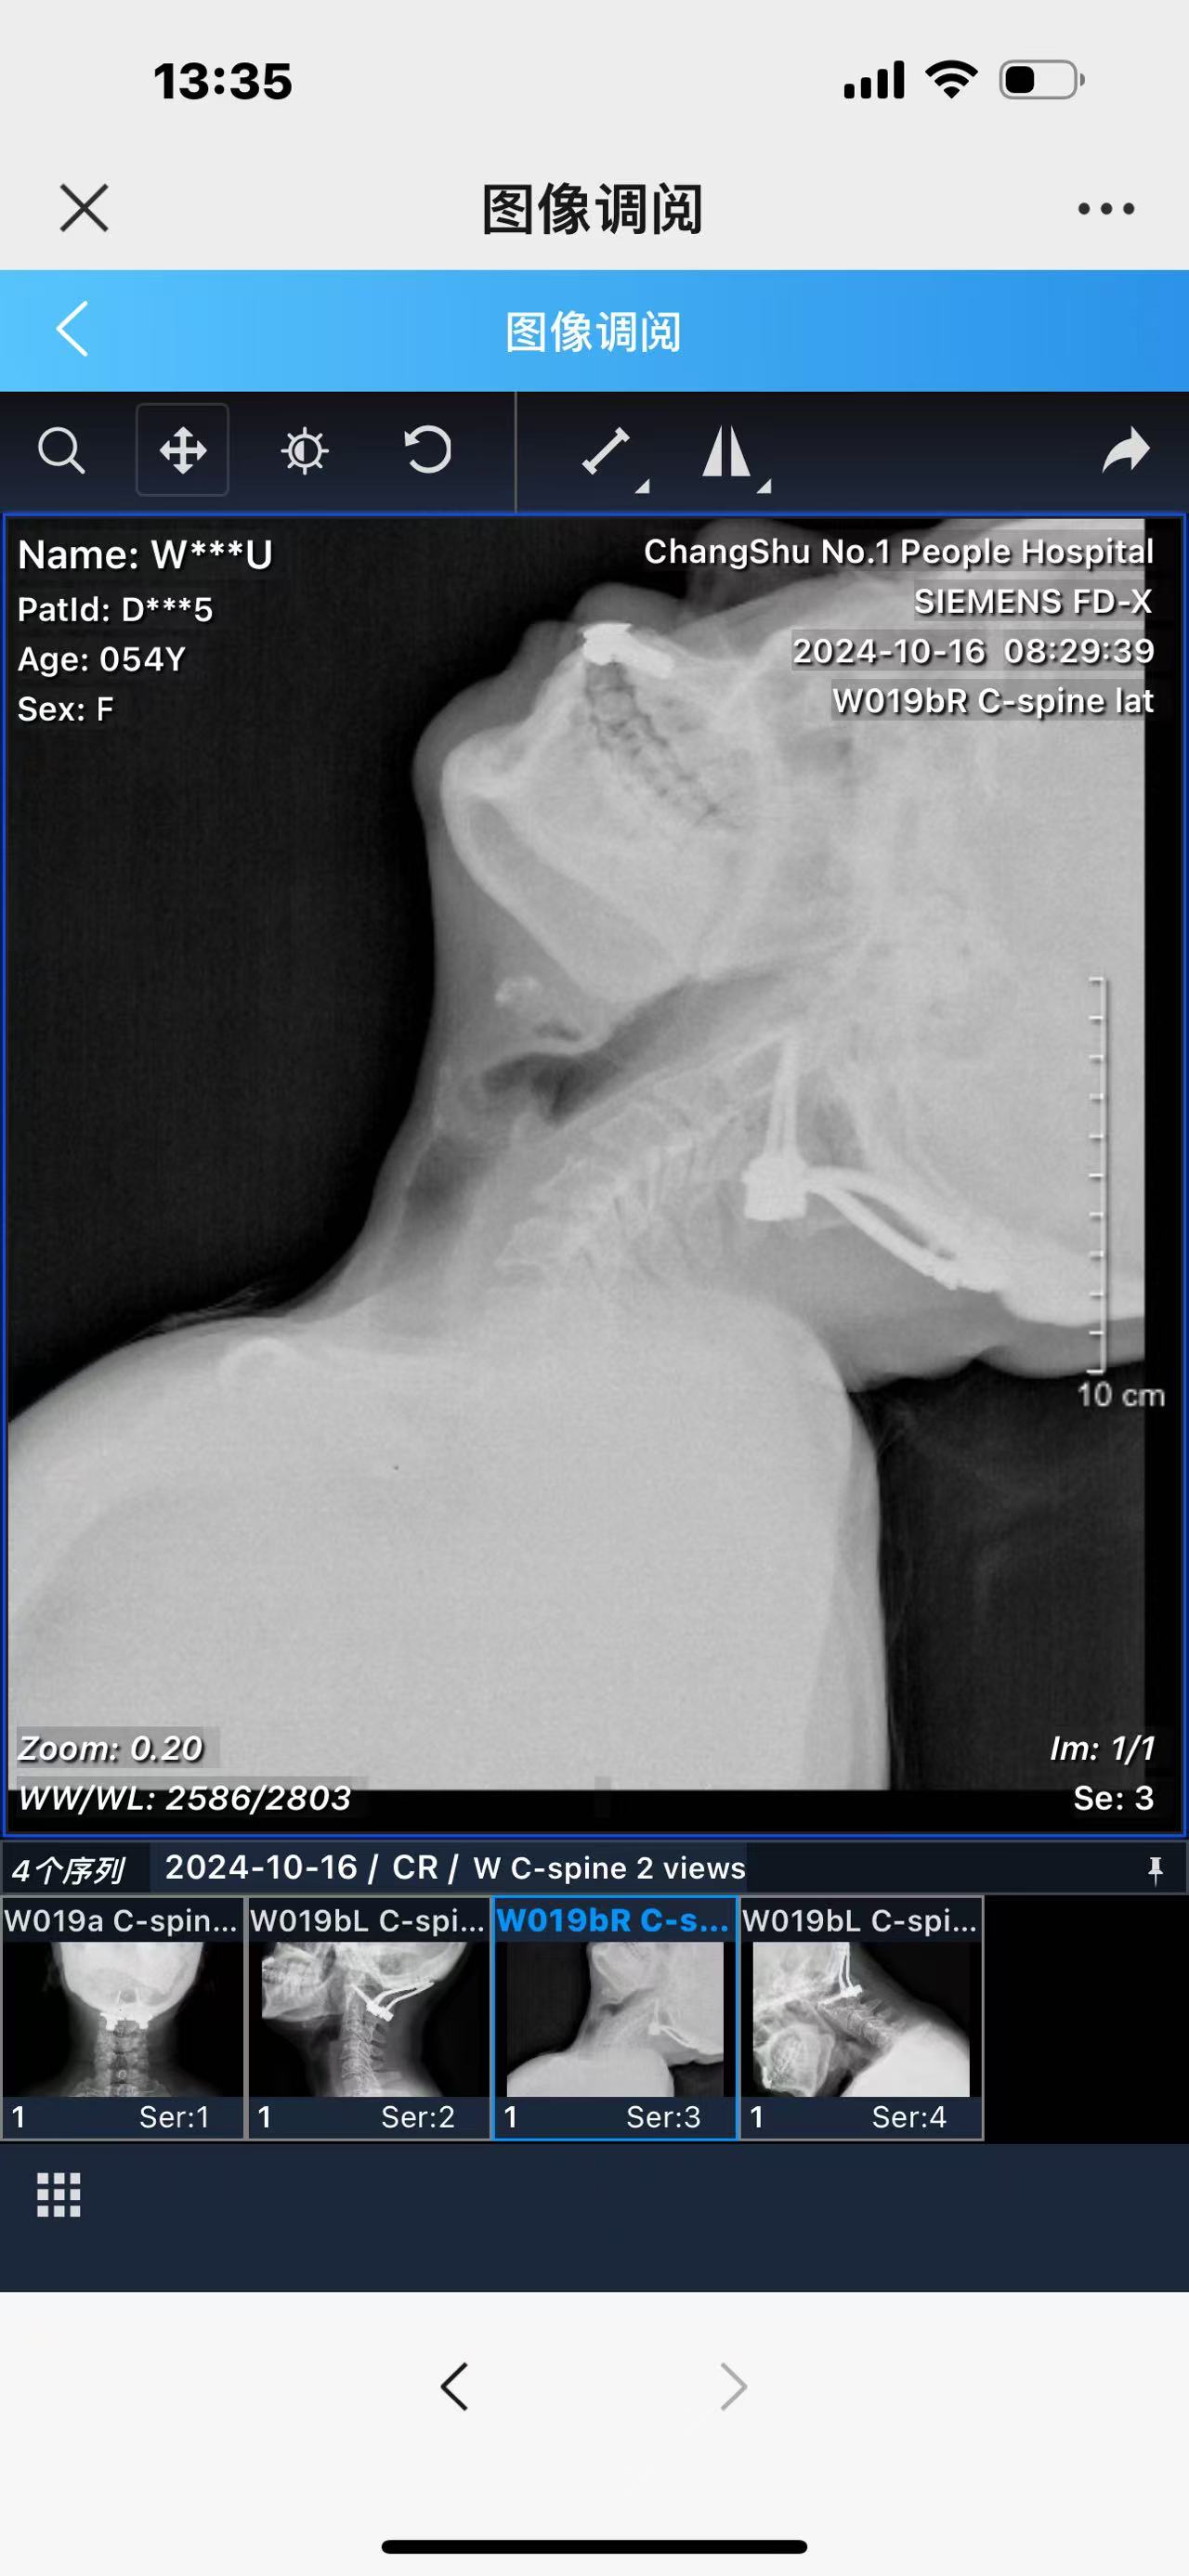

• 术后影像: